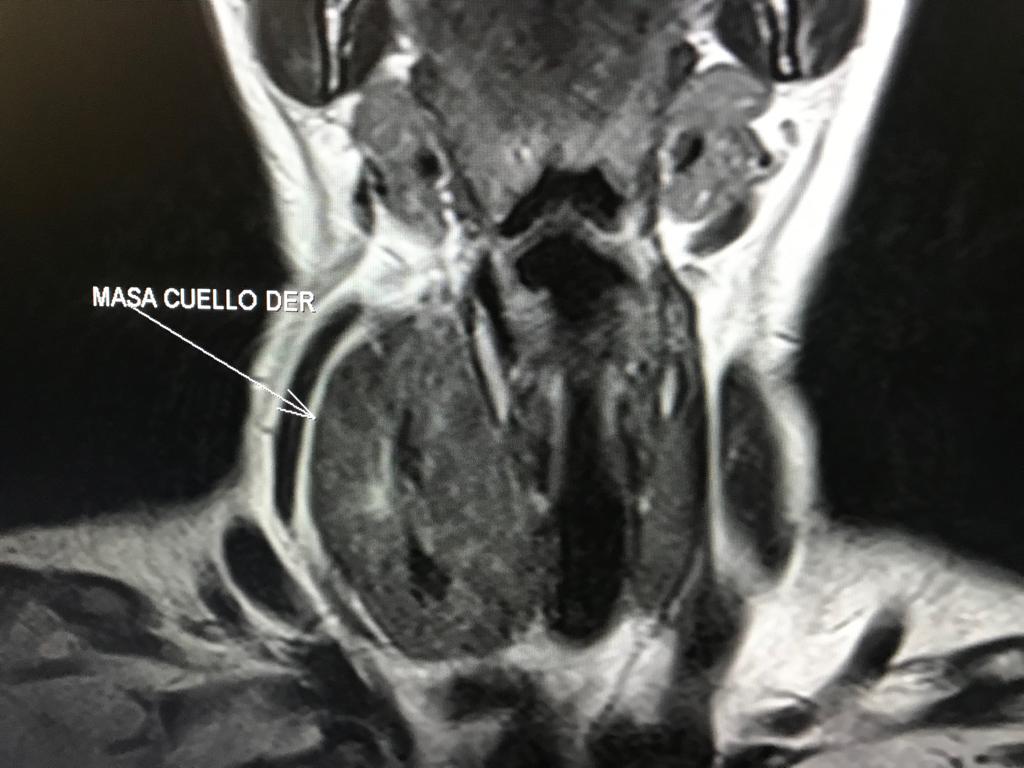

RM CEREBRAL

RM CEREBRAL Meningioma Lipomatoso: Es una variante atípica del meningioma. Los meningiomas constituye el tumor  intracraneal primario más frecuente (15-20%) y el tumor extraparenquimatoso más frecuente en el compartimento supratentorial en el adulto. Es por tanto una...